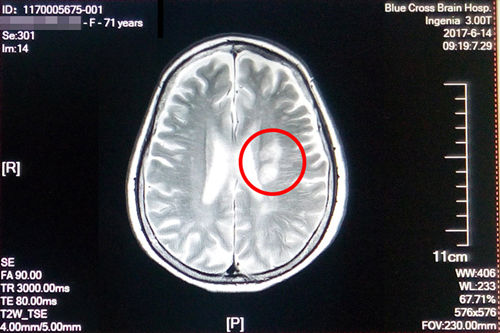

术前磁共振影像显示:患者多发性大面积脑梗

盛阿姨今年五月脑梗复发,在其他医院经过治疗后有所好转,在之后的康复治疗过程中病情又加重了,焦急的家属联系到了“蓝十字”。经过神经内科初步检查诊断,盛阿姨左侧侧脑室旁脑梗塞(急性期),脑干、双侧基底节区及额、顶叶多发腔隙性梗塞;大面积脑梗还造成了言语不清和偏瘫。入院时,右上肢肌力3级,左上肢肌力4级,双下肢肌力3级,因此无法行走,病情较重。